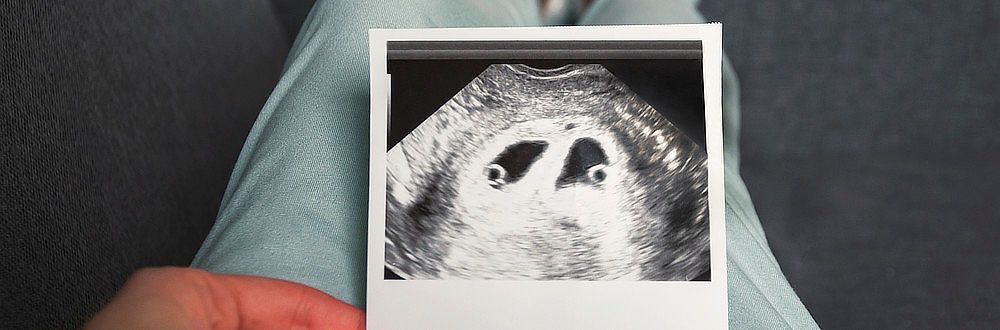

Žena s vícečetným těhotenstvím může do 12. týdne požádat o umělé přerušení těhotenství, resp. o snížení počtu plodů v děloze. Redukce se provádí ambulantně podáním léčivého přípravku plodu.

Do 12. týdne těhotenství může těhotná písemně požádat o umělé přerušení těhotenství bez udání důvodů. Tímto výkonem se snižuje počet plodů v děloze. Není-li jiný důvod, ukončí se vývoj plodu uloženého blíže dnu děložnímu.

Redukce vícečetného těhotenství se provádí na konci I. trimestru obvykle ambulantně. Po dezinfekci břicha je pod ultrazvukovou kontrolou dlouhou tenkou jehlou přes stěnu břišní aplikován plodu léčivý přípravek, po kterém ustane jeho srdeční činnost. Nepoužívá se žádná anestezie, protože výkon je bolestivostí srovnatelný s odběrem krve ze žíly. Odumřelý plod zůstává v děloze.